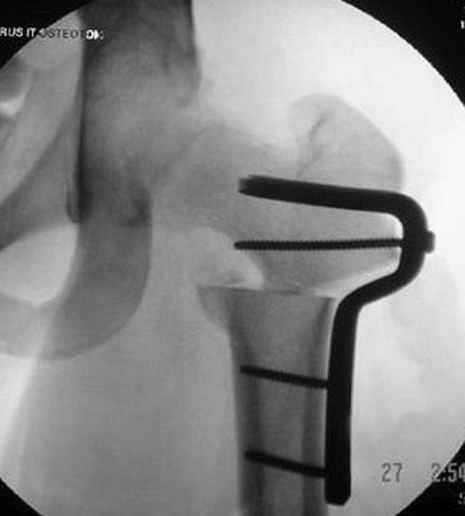

На рисунке N1 предоперационный план лечения ложного сустава шейки бедра- линия ложного сустава, угол и направление введения импланта, клиновидная остеотомия в градусах и миллиметрах, второй снимок после коррекции, расчет, на сколько удлиняется конечность и размеры импланта;

N3 рисунок окончательный снимок, после операции моя рентгенограмма должен выглядеть примерно как эта картина. На N4 снимке клин перед удалением; N5 послеоперации 3 нед.; N6 окончательная рентгенограмма.